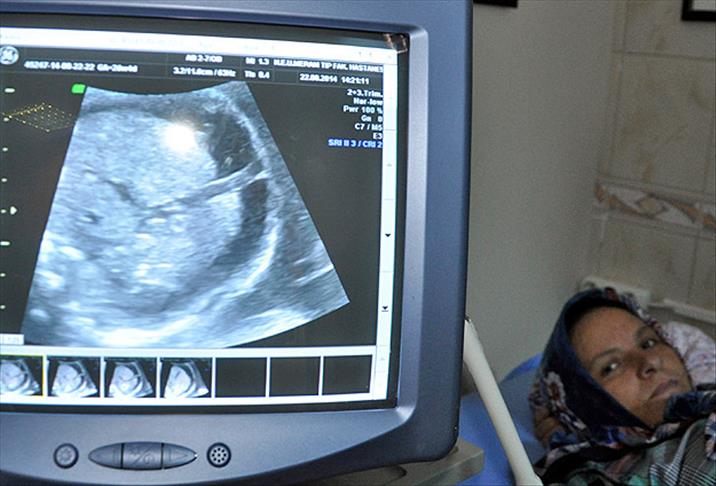

Bebekleri kansızlık nedeniyle ölen Sağlamer çiftinin, anne karnındaki 6 aylık bebeklerine de Necmettin Erbakan Üniversitesi Meram Tıp Fakültesi Hastanesinde aynı rahatsızlık teşhisi konuldu.

Teşhiste geç kalındığı için önceki bebeklerini kaybeden Nevin Sağlamer, yine aynı acıyı yaşayacağı düşüncesiyle çok korktu. Hastanenin Kadın Hastalıkları ve Doğum Anabilim Dalı Öğretim Üyesi Prof. Dr. Ali Acar, bebeğe iki milimetre çapındaki damardan başarılı şekilde kan nakli gerçekleştirdi.

Acar, anne karnında belirli aralıklarla 5 kez kan verdiği bebeğin ölmesinin önüne geçti.